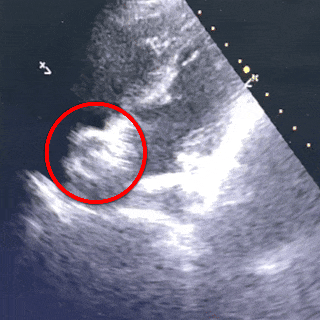

四腔心切面

封堵器锁定成型后,超声下多切面确认封堵器盘面贴合,稳定夹持缺损

超声下可见封堵器稳定夹持在房间隔两侧,盘面贴合,形态良好